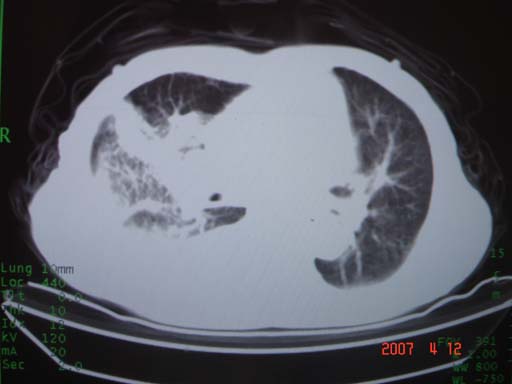

帮我 看看。男77岁咳嗽咯血2月发热2周!病人一般情况可 口痰为鲜红,有点象洗肉水(我看见他吐的痰了)

病灶局限在右肺中上叶,呈大片状实变影,内见空气支气管征,支气管分支较柔软,纵隔内未见肿大淋巴结.支持:感染性病变_1 大叶性肺炎.2 干酪性肺炎.

优先考虑右上肺干酪性肺炎并同侧中叶播散、胸腔积液。分析:右膈肌未见升高、纵隔未见明显右移,胸部各组淋巴结未见可疑肿大,中叶可见支气管铸形,肺野、肺门未见可确定肿块。

单从影像学上来看,该病人应首先考虑,右上肺感染(干酪性肺炎可能大)伴有右侧胸腔积液,理由如下:

1.病灶整体成宽基底征,而未见块状影

2.病灶内的透光区并不是含气支气管征,而像是坏死的肺组织后形成的

3.无肺不张的表现

4.纵隔那未见明显肿大淋巴结

结合病史,该病人尚需作进一步检查胸水,支气管镜,查痰等

有点象洗肉水的痰,其来源应当是实变引起的血细胞渗出导致,可见支气管气象,实变区有虫蚀状空洞,有明显胸腔积液,未见明显肺门区肿块影,考虑继发型肺结核,干酪性肺炎

右肺上叶实变,实变范围如此之大,如果用肺癌解释的化,应该是比较大的支气管开口发生完全阻塞,但观察上叶前后段支气管还是比较通畅,所以应考虑感染性病变,大叶性肺炎可能,建议抗炎治疗后复查。